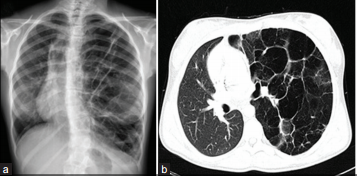

2. Malformacion adenomatoide quistica congenita

1. Causas

1. Dilatacion anormal vias respiratorias pequeñas y proliferacion adenomatoide

2. Asociada a

1. Infecciones pulmonares frecuentes

1. Dificultad respiratoria

2. ¿Nuevo Termino?

1. Malformaciones congénitas de las vías respiratorias pulmonares

2. Clasificacion

1. Tipo 1

1. Una o mas lesiones quisticas grandes (10cm) recubiertas por celulas pseudoestratificadas

1. 60-70% de todos los casos

1. Tipo 2

1. Hallazgos

1. Masa multiquistica con aire

1. Area focal de consolidacion

2. Tipo 3

1. Hallazfos

1. Unicamente histologico

1. Quistes Microscopicos